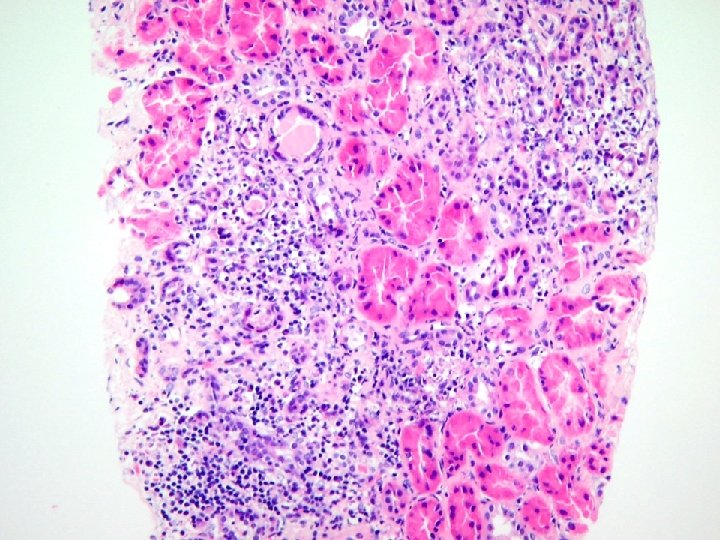

• LRD kidney transplant was performed October 25, 2000. • Rising creatinine about 2 months later lead to transplant biopsy • Demonstration of crystals which lead to investigations resulting in diagnosis of primary oxaluria (type I) • Creatinine continue to rise.

st Renal biopsies after 1 Tx Indication Banff Deposits time of Tx G 0 I 0 T 0 V 0 AH 2 - U 00 -14762 (~ 2 creat 120 weeks post-Tx) G 0 I 0 T 0 V 0 AH 2 Focal tubular calcifications U 00 -15830 (~ 1 creat 160 month post-Tx) G 0 I 0 T 0 V 0 AH 2 Acute tubular injury with calcium oxalate deposition creat 280 G 0 I 0 T 0 V 0 AH 2 Extensive tubular deposition of calcium oxalate consistent with oxalosis U 00 -14101 U 01 -253 (~ 2 months post. Tx) Scanned slide

• Combined liver/kidney transplant June 21, 2003 with initial serum creatinine of 80 µmol/L. • First post transplant biopsy done when creatinine rose to 120 µmol/L

nd Renal biopsies after 2 Tx U 03 -9704 Indication Banff Deposits time of Tx G 0 I 0 T 0 V 0 AH 1 - U 03 -12130 creat 120 N. S. findings (~ 6 weeks post with G 0 CG 0 I 1 CI 1 T 0 proteinuria CT 1 V 0 CV 1 AH 0 -Tx) MM 0 tubular calcium phosphate deposition

nd Renal biopsies after 2 Tx U 03 -9704 Indication Banff Deposits time of Tx G 0 I 0 T 0 V 0 AH 1 - U 03 -12130 creat 120 N. S. findings (~ 6 weeks post with G 0 CG 0 I 1 CI 1 T 0 proteinuria CT 1 V 0 CV 1 AH 0 -Tx) MM 0 U 03 -15919 (~ 4 months post-Tx) c reat 180 post stent change acute bacterial interstitial nephritis G 0 CG 0 I 3 CI 2 T 1 CT 2 AH 2 MM 0 tubular calcium phosphate deposition extensive calcium phosphate and calcium oxalate deposition

nd Renal biopsies after 2 Tx U 03 -9704 Indication Banff Deposits time of Tx G 0 I 0 T 0 V 0 AH 1 - U 03 -12130 creat 120 N. S. findings (~ 6 weeks post with G 0 CG 0 I 1 CI 1 T 0 proteinuria CT 1 V 0 CV 1 AH 0 -Tx) MM 0 tubular calcium phosphate deposition U 03 -15919 (~ 4 months post-Tx) c reat 180 post stent change acute bacterial interstitial nephritis G 0 CG 0 I 3 CI 2 T 1 CT 2 AH 2 MM 0 extensive calcium phosphate and calcium oxalate deposition U 04 -6303 (~ 10 months post-Tx) ureteral obstruction acute rejection IA G 0 CG 0 I 3 CI 2 T 2 CT 2 V 0 CV 0 AH 1 MM 0 no crystals in kidney but present in ureter